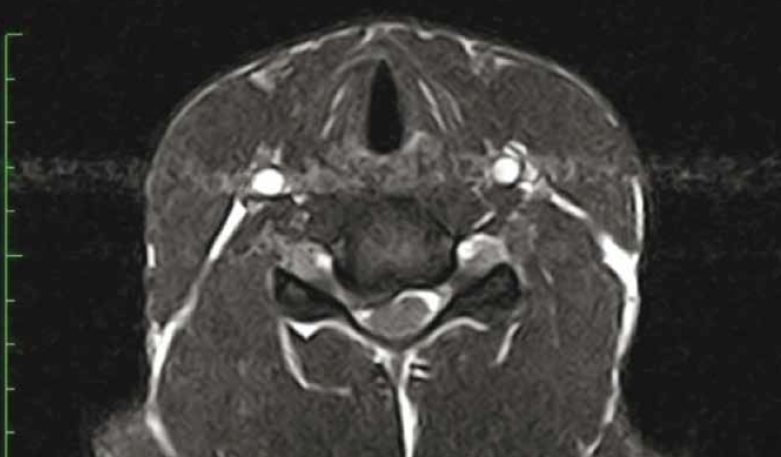

Scanner rachis cervical. Full labeled MRI Normal anatomy of the cervical spine (cervical vertebrae) using crosssectional (axial, sagittal and coronal) magnetic resonance where the vertebrae, the nervous system, the intervertebral discs and the zygapophyseal joints and the vascularization can be differentiated This imaging was created from sagittal T1weighted sequences and T2 reconstructions. A CT cervical spine is performed in the radiology department scanning room, with the patient lying flat (supine) on a CTtable The head is placed in a comfortable ‘docking pillow’ and the CT scanner gantry (donut) passess over and around the patient to perform the scan The gantry travels over the patient from the level of the jaw to the. Le Rachis Cervical Est Bien Entendu Palpe Et Immobilise (collier Rigide) Examen Du Thorax Fractures De Cotes, pdf 110 pages 2,13 MB Télécharger Scanner Abdominal Video Scanner Abdominal Notices & Livres Similaires radioanatomie du rachis stutz.

Rachis au scanner Les examens ont été réalisés par un scanner multi barrette CT brillance 6 de marque Philips suite rachis cervical 43%(n=43), charnière cervicodorsale 2%, rachis. Sources welche Teile der Wirbelsäule werden gescannt ?. A cervical MRI scans the soft tissues of your neck and cervical spine The cervical spine is the portion of your spine that runs through your neck A cervical spine MRI scan is used to help diagnose.